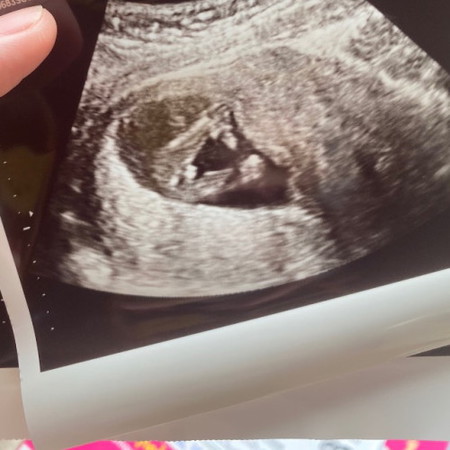

แม่ๆช่วยดูหน่อยค่า

น้องเป็นผญ หรือผช คะ คุณแม่ท่านไหนมีประสบการณ์มาแชร์กันได้ค่ะ

มีความเป็นไปได้ว่าน้องเป็นผู้ชายค่ะ ต้องมารอดูหลัง20Wขึ้นไปถึงจะเริ่มชัวร์แล้วนะคะคุณแม่☺️

ผู้ชายค่ะเหมือนเห็นไข่น้อง

น่าจะผู้ชายนะคะแม่มีกลมๆ

น้องหน้าจะเป็นผู้ชายค่ะ

น่าจะชายคะเหมือนไข่โผล่

น้องมีใข่ด้วย ผู้ชาย100%คะ

ผู้ชายค่ะเห็นไข่โผล่

น้องดูมีไข่นะคะแม่